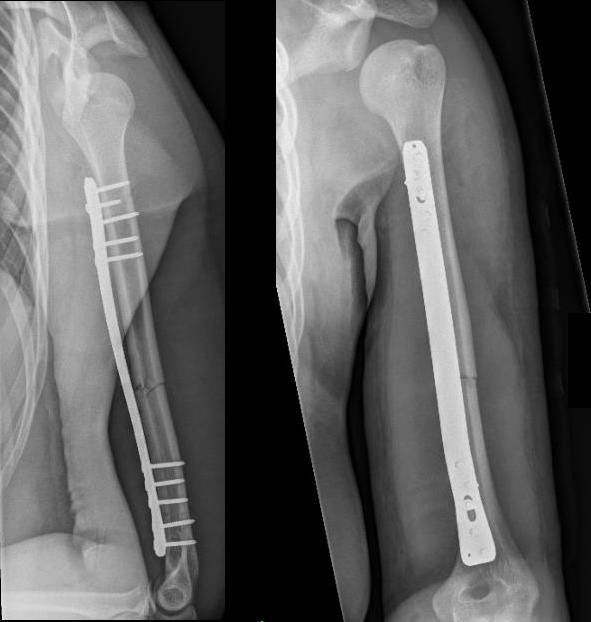

Failure of fixation

Complications of ORIF

Nonunion

Revision of fixation to longer posterior plate